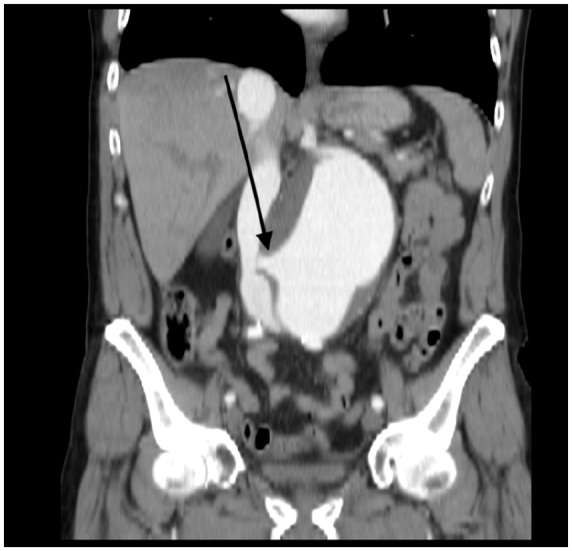

Abdominal aortic aneurysm (AAA) is a potentially life-threatening condition characterized by abnormal dilation of the abdominal aorta, typically due to chronic arterial wall degeneration. Aorto-caval fistula (ACF) is a rare but serious complication of AAA, occurring in less than 1% of cases overall, with incidence increasing in the setting of rupture. ACF involves the formation of an abnormal communication between the abdominal aorta and the inferior vena cava (IVC), resulting in blood shunting from the arterial to the venous system. This can cause reduced organ perfusion, high-output cardiac failure, and multiorgan dysfunction. We present the case of a 65-year-old hypertensive male with a known AAA who presented with 2 days of abdominal pain but no systemic or gastrointestinal symptoms. Physical examination revealed periumbilical tenderness, while laboratory results were normal. Contrast-enhanced computed tomography of the abdomen revealed a large (10 cm) infrarenal AAA with evidence of rupture, mural thrombus, and a fistulous connection to the IVC. The patient underwent successful endovascular repair with complete resolution of the aneurysm and fistula, as shown in follow-up imaging. This case highlights the importance of high clinical suspicion and the role of early imaging in diagnosing ACFs, even in the absence of classical signs or lab abnormalities. The aim is to raise awareness of such atypical presentations and emphasize our case's uniqueness in its silent, stable, yet severe presentation.

Abstract Image